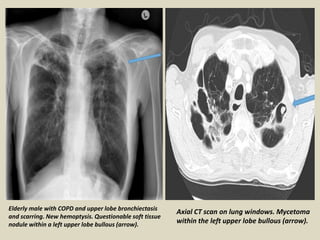

Elderly male with COPD and upper lobe bronchiectasis

and scarring. New hemoptysis. Questionable soft tissue

nodule within a left upper lobe bullous (arrow).

Axial CT scan on lung windows. Mycetoma

within the left upper lobe bullous (arrow).

Coronal reformat demonstrating bilateral upper lobe bullae,

scarring and bronchiectasis with a fungus ball on the left (arrow).

Mycetoma formation (Fungus ball)

Aspergillus fumigatus is a fungus that may colonise dilated

airways or bullae/cavities. It is an important cause of

hemoptysis.